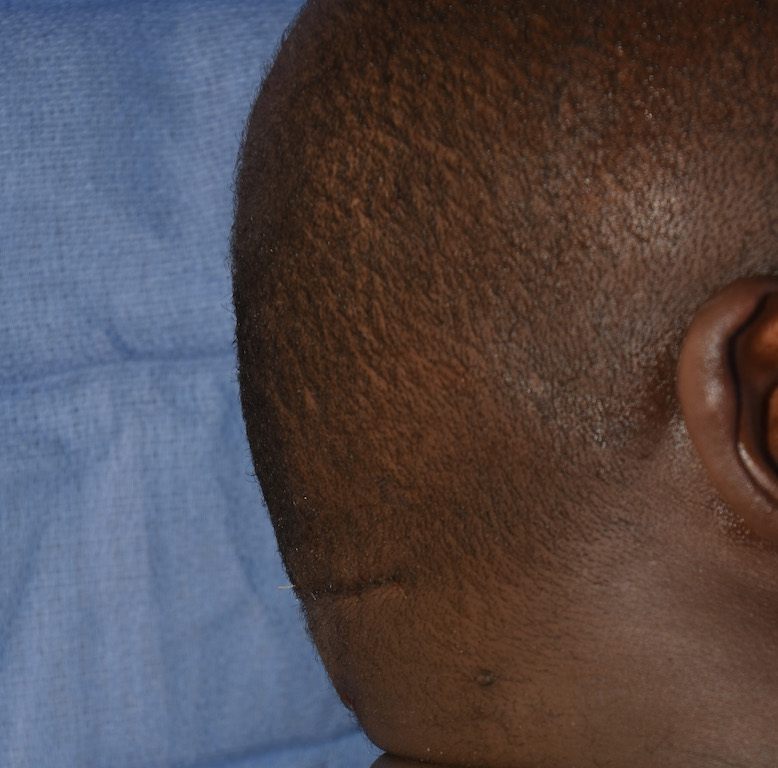

Patient 28

Desire for rounder shape to the top of the head from a congenital parasagittal deficiency skull shape.

Custom skull implant designed to fill in the parasagittal deficiencies.

Desire for rounder shape to the top of the head from a congenital parasagittal deficiency skull shape.

Custom skull implant designed to fill in the parasagittal deficiencies.